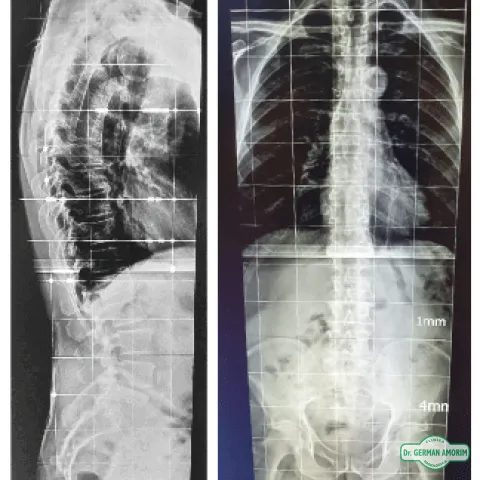

Radiografías

Estudios Simples

Estudios Simples Especializados